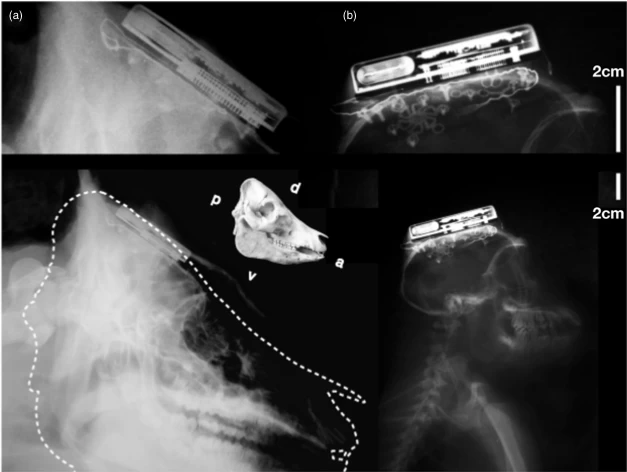

2.2インチのデバイスは、約16ヶ月前からブタ3匹とアカゲザル3匹の頭部に埋め込まれており、動物の脳内部の仕組みに関する詳細な情報を提供しています。このデバイスの開発を監督したブラウン大学工学部教授のアルト・ヌルミッコ氏は、この電子機器は携帯電話のそれよりもはるかに複雑であるにもかかわらず、消費電力はごくわずかだと述べています。

このシステムの心臓部は、大脳皮質に埋め込まれた錠剤サイズの電極チップです。ニューロン群からの信号は、プロセッサ、リチウムイオン電池、無線通信機、赤外線送信機を内蔵したチタン製のボックスに送られます。このデバイスは無線誘導充電式で、消費電力は100ミリワット未満です。ヌルミッコ氏はこれを重要なブレークスルーと表現しました。充電には数時間かかり、その間にブタとサルの皮膚はかなり熱くなるため、研究チームは頭から冷たい生理食塩水をかけ、温度を下げてあげました。

この装置は、3.2GHzと3.8GHzのマイクロ波周波数を用いて24Mbpsでデータを送信します。装置全体は密閉され、人体への侵入を防ぐ構造になっており、人体に埋め込まれた最初の電気機器であるペースメーカーよりもはるかに複雑です。